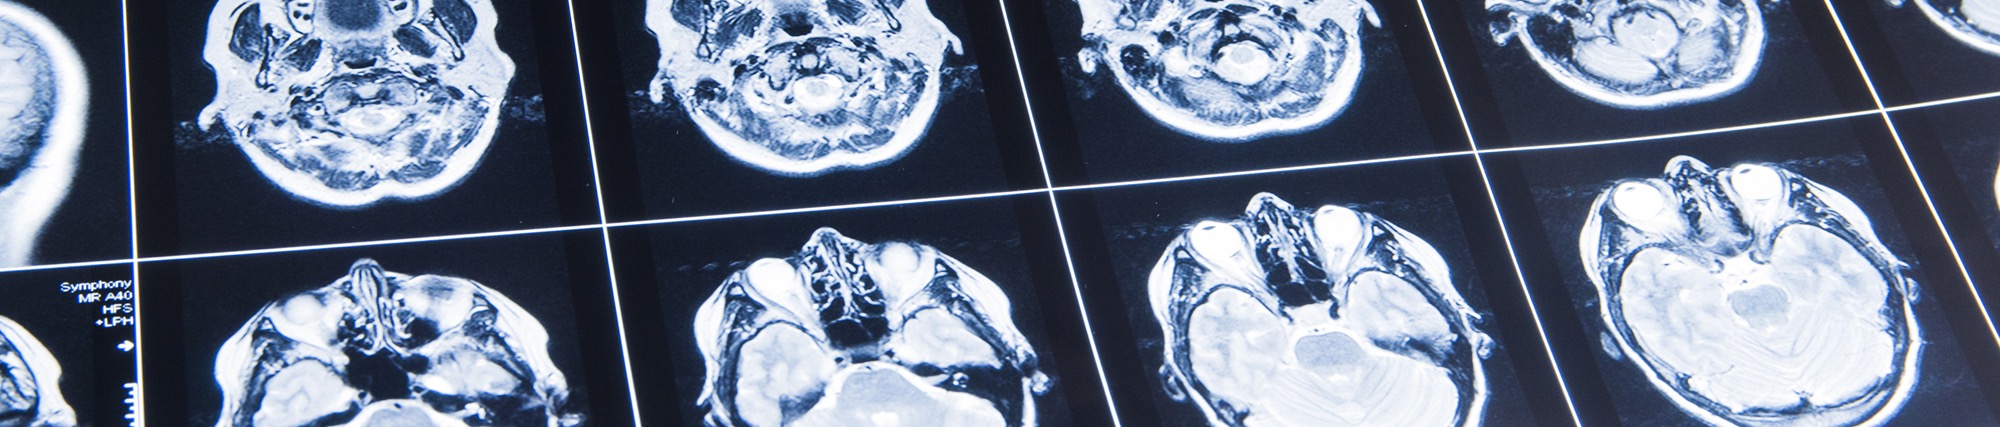

Traumatic Brain Injury

A traumatic brain injury, or TBI, is, quite literally, a jarring experience. A TBI can occur whenever you suffer a severe blow to the head, which can, in turn, damage the brain. TBIs are disturbingly common: Each year, nearly two million Americans suffer from some form of severe head injury. More than 50,000 people die nationwide from TBI, and thousands more suffer long-term disability as a result of brain injury. If you or a loved one has suffered a TBI as a result of someone else’s negligent action, you deserve compensation for your injury. Levinson Law, P.C., is here to help.

Traumatic brain injuries can result from all sorts of accidents. According to the U.S. Centers for Disease Control (CDC), a TBI is “caused by a bump, blow, or jolt to the head or a penetrating head injury that disrupts the normal function of the brain.” Any incident that leads to sudden and extreme head trauma is liable to cause TBI, even when the collision does not appear very severe. Even mild TBIs can cause a concussion. More severe TBI can lead to loss of consciousness, permanent brain damage, loss of memory, coma, and a variety of other serious issues.